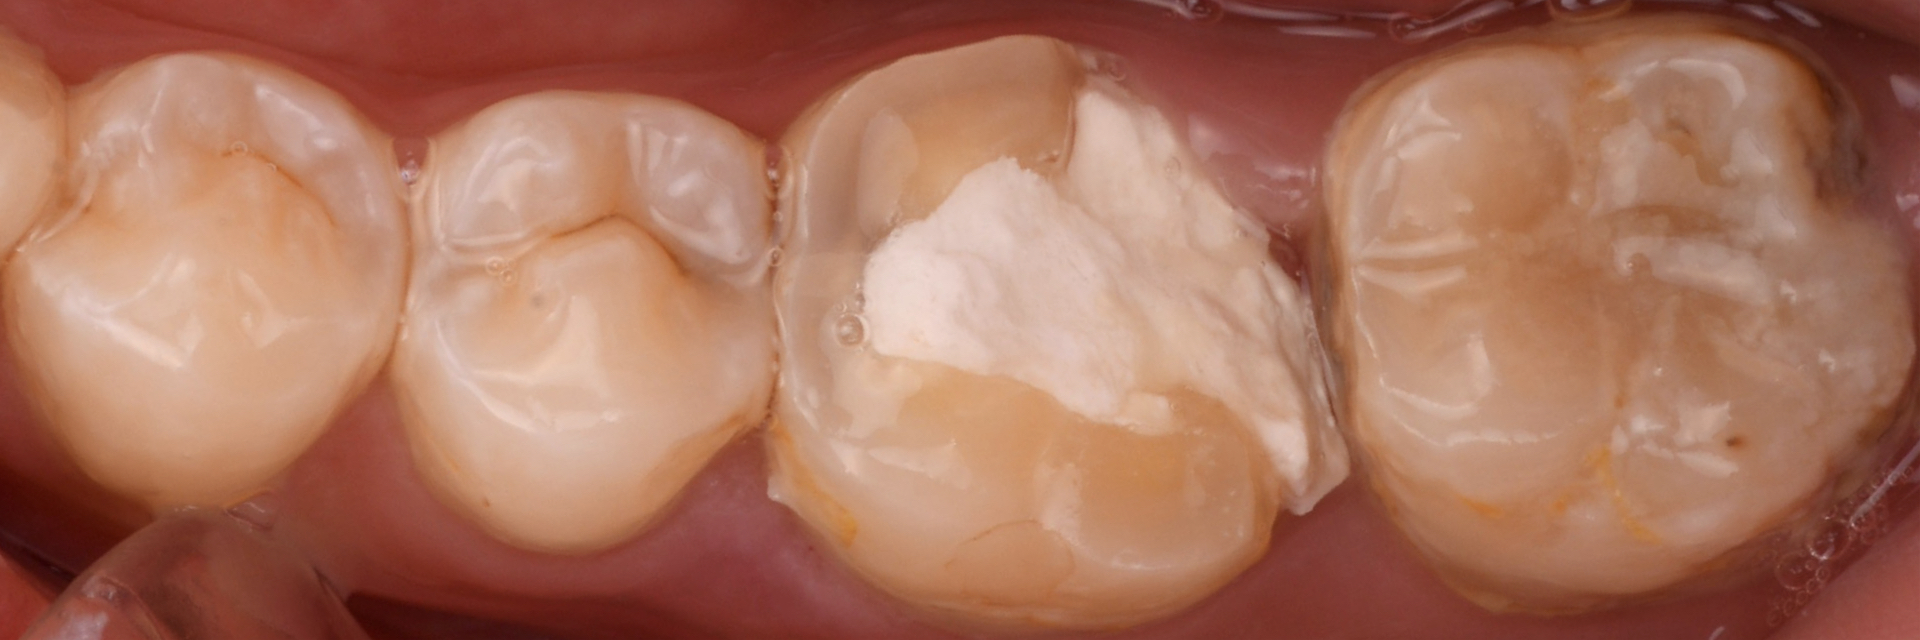

治療後

治療で得られるメリット:審美的、再度虫歯になるリスクがほぼない

| 治療内容 | セラミックによる虫歯治療 ラバーダム防湿下で再度治療が必要にならないよう、徹底的に治療 |